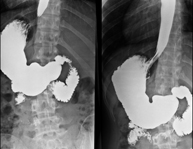

Tècnica que usa els raigs X a través de la qual s'obtenen imatges de la columna lumbar per al seu estudi. - TEGD (trànsit esòfag-gastro-duodenal)

Prova diagnòstica que consisteix en obtenir imatges radiològiques en moviment de l'esòfag, estómac i duodè mitjançant l'ús de raigs X (fluoroscòpia) i d'un contrast opac baritat que s'administra per via oral. - Trànsit intestinal

Prova diagnòstica que consisteix en obtenir imatges radiològiques en moviment de l'esòfag, estómac, duodè i intestí prim mitjançant l'ús de raigs X (fluoroscòpia) i d'un contrast opac baritat que s'administra per via oral. - Ènema opac doble contrast

Prova diagnòstica que consisteix en obtenir imatges radiològiques de l'intestí gros (còlon i recte) mitjançant l'ús de raigs X. S'utilitza un contrast opac que s'administra a través del recte en forma d'ènema i també s'introdueix aire per expandir el còlon.